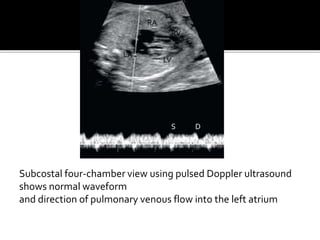

Subcostal four-chamber view using pulsed Doppler ultrasound

shows normal waveform

and direction of pulmonary venous flow into the left atrium

Subcostal four-chamber viewusing pulsed Doppler ultrasound shows normal waveform and direction of pulmonary venous flow into the left atrium RA LA RV LV S D